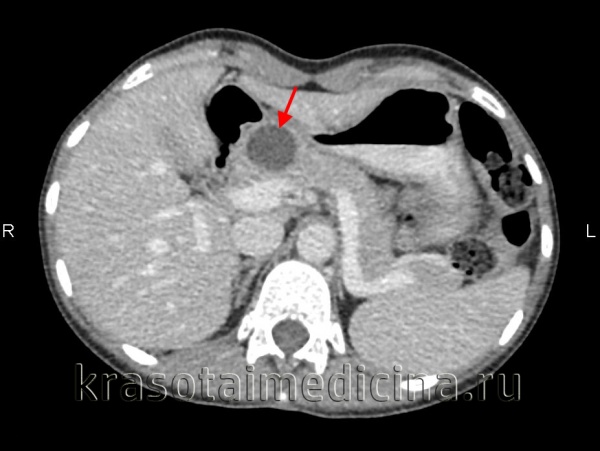

3. Компьютерная топография более чувствительна по сравнению с УЗИ. КТ позволяет проводить дифференциальную диагностику псевдокист. Кроме этого возможна пункция и дренирование псевдокист под контролем КТ.

КТ органов брюшной полости. Псевдокиста поджелудочной железы у пациента после приступа острого панкреатита